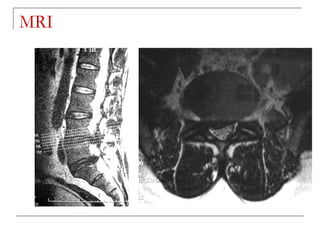

MRI

   -better soft tissue visualization

   -disc

   -ligaments (ALL,PLL)

   -nerves (spinal cord, roots)

   -bone marrow

   -pus collection

MRI  -better soft tissue visualization  -disc  -ligaments (ALL,PLL)  -nerves (spinal cord, roots)  -bone marrow  -pus collection